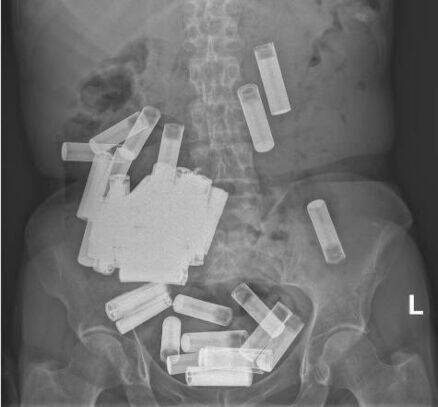

爱尔兰66岁老妇吞下55颗电池 胃下垂到耻骨附近

爱尔兰都柏林圣文森医院近来收治一名罕见病例,一名66岁老妇竟然吞下55颗3号和4号电池,胃部甚至下垂到了耻骨附近。

根据《爱尔兰检查者报》报道,圣文林医院放射科医师和直肠外科医师团队,将病例发表在本月的《爱尔兰医学期刊》上,当中表示妇人吞下55颗电池应该创下类似病例的最高纪录。

医院收治老妇时,由于没有堵塞、穿也且电池结构完整,因此初步采取保守治疗,让老妇自然排出5颗电池。

不过接下来电池在老妇的消化系统中停止不前,患者出现腹痛和食欲不振的症状,因此院方决定开刀取出电池,最后在胃里一共拿出46颗电池,另4颗由于被挤入直肠,因此从肛门用镊子取出。

圣文林医院表示,患者在手术后顺利康复,同时也强调吞下电池可能会导致多种严重并发症,包括黏膜损伤、穿也和堵塞等等。